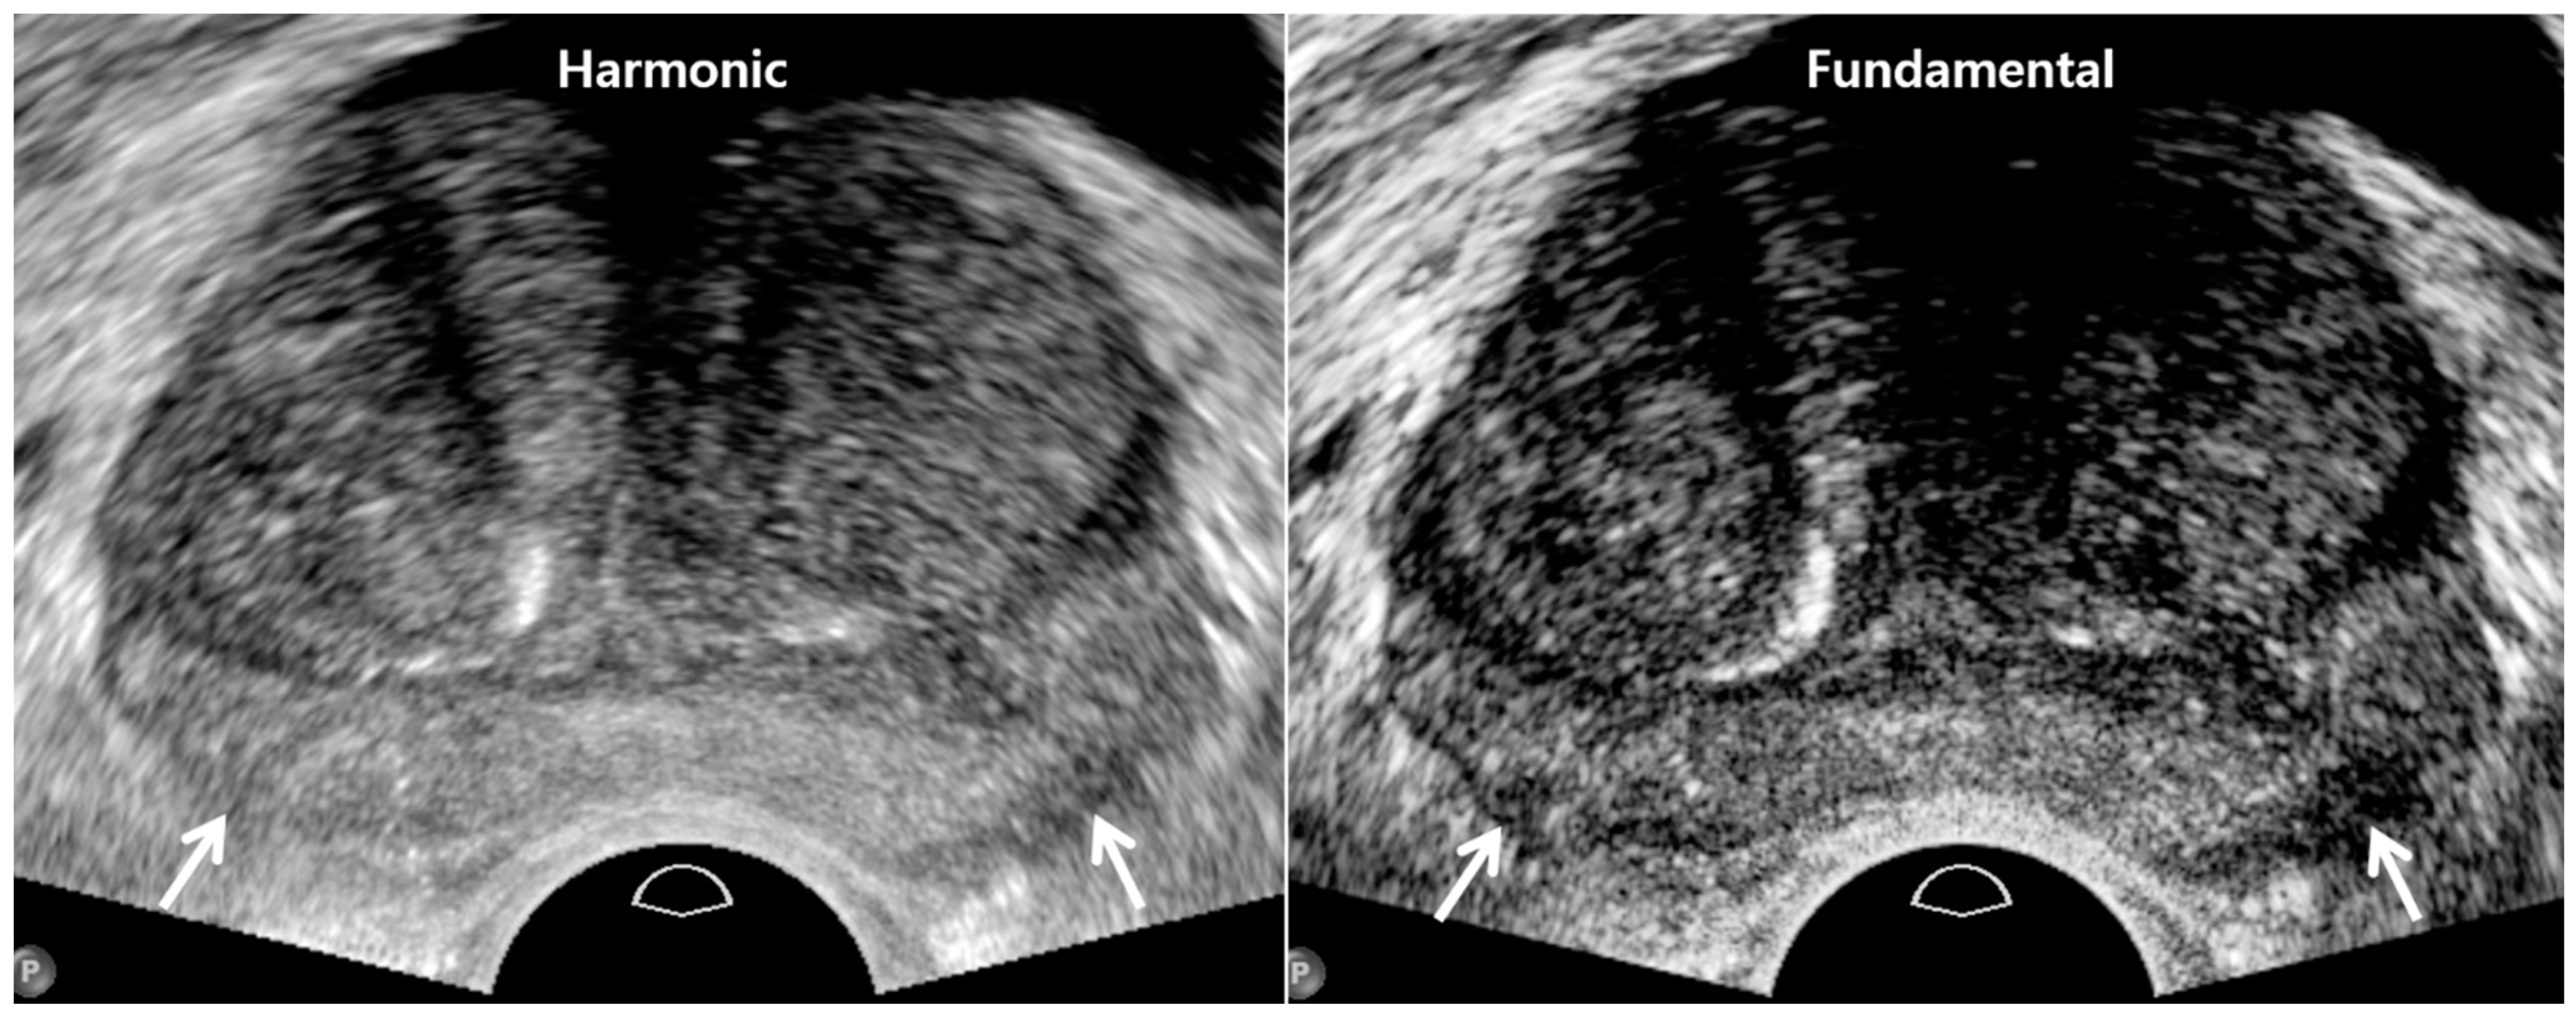

2. TRUS Imaging Protocols

| US sequence | Harmonic imaging | Fundamental imaging |

| US artifacts | Rare | Frequent |

| Dynamic range | High | Low |

| Image resolution | High | Low |

| Tissue contrast | Low | High |